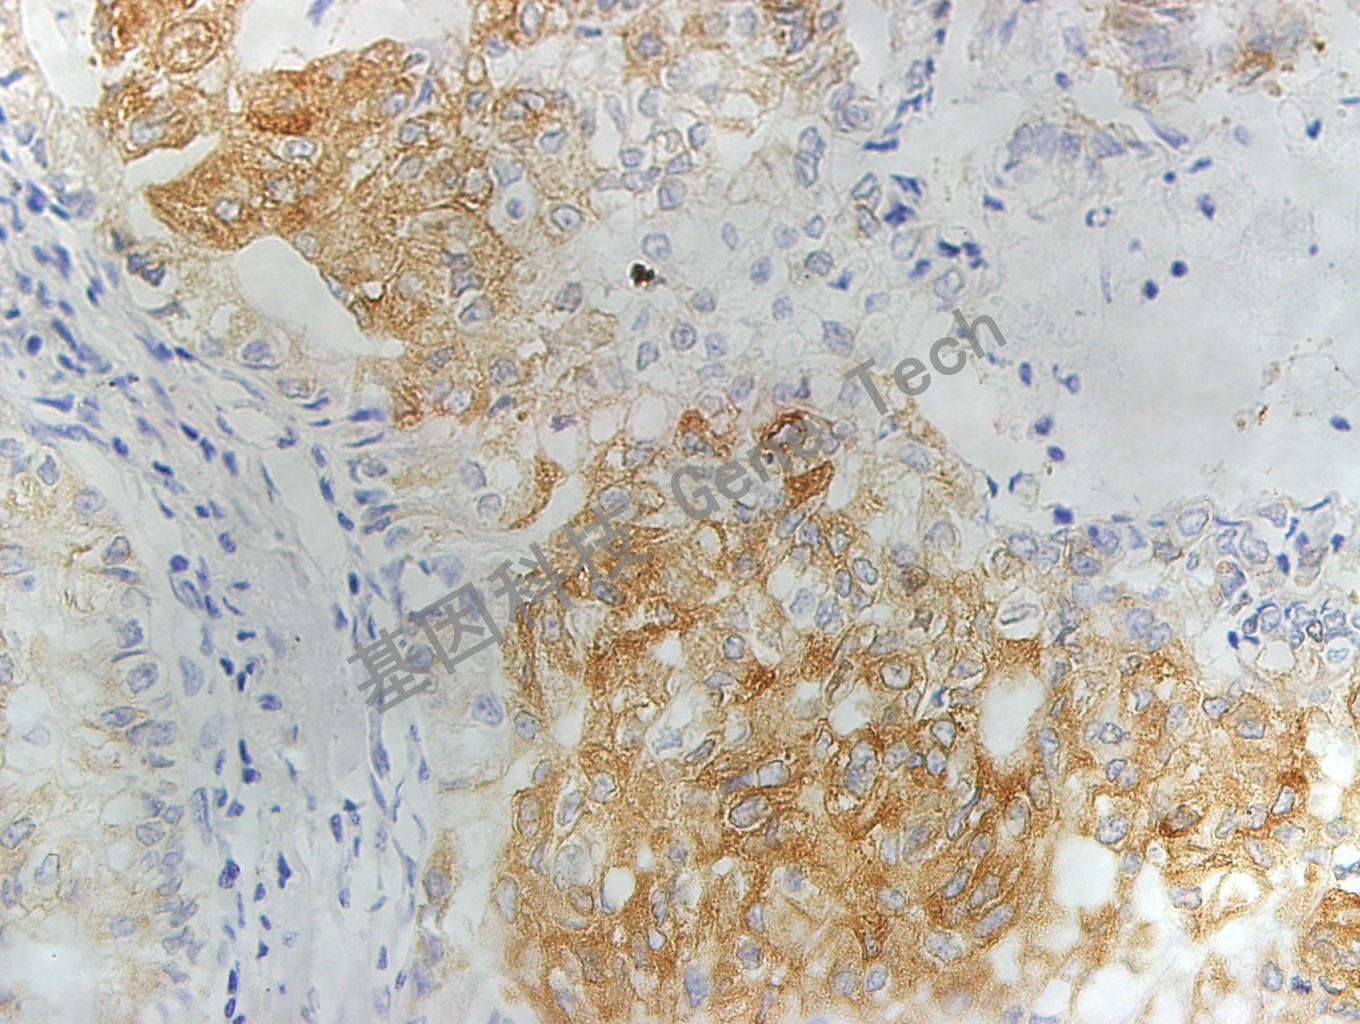

MRP1 GT2015 10X B5肺_副本.jpg肺癌石蜡切片,用 MRP1(GT2015)染色,细胞浆阳性,DAB 显色。

MRP1 GT2015 40X B5肺_副本.jpg肺癌石蜡切片,用 MRP1(GT2015)染色,细胞浆阳性,DAB 显色。